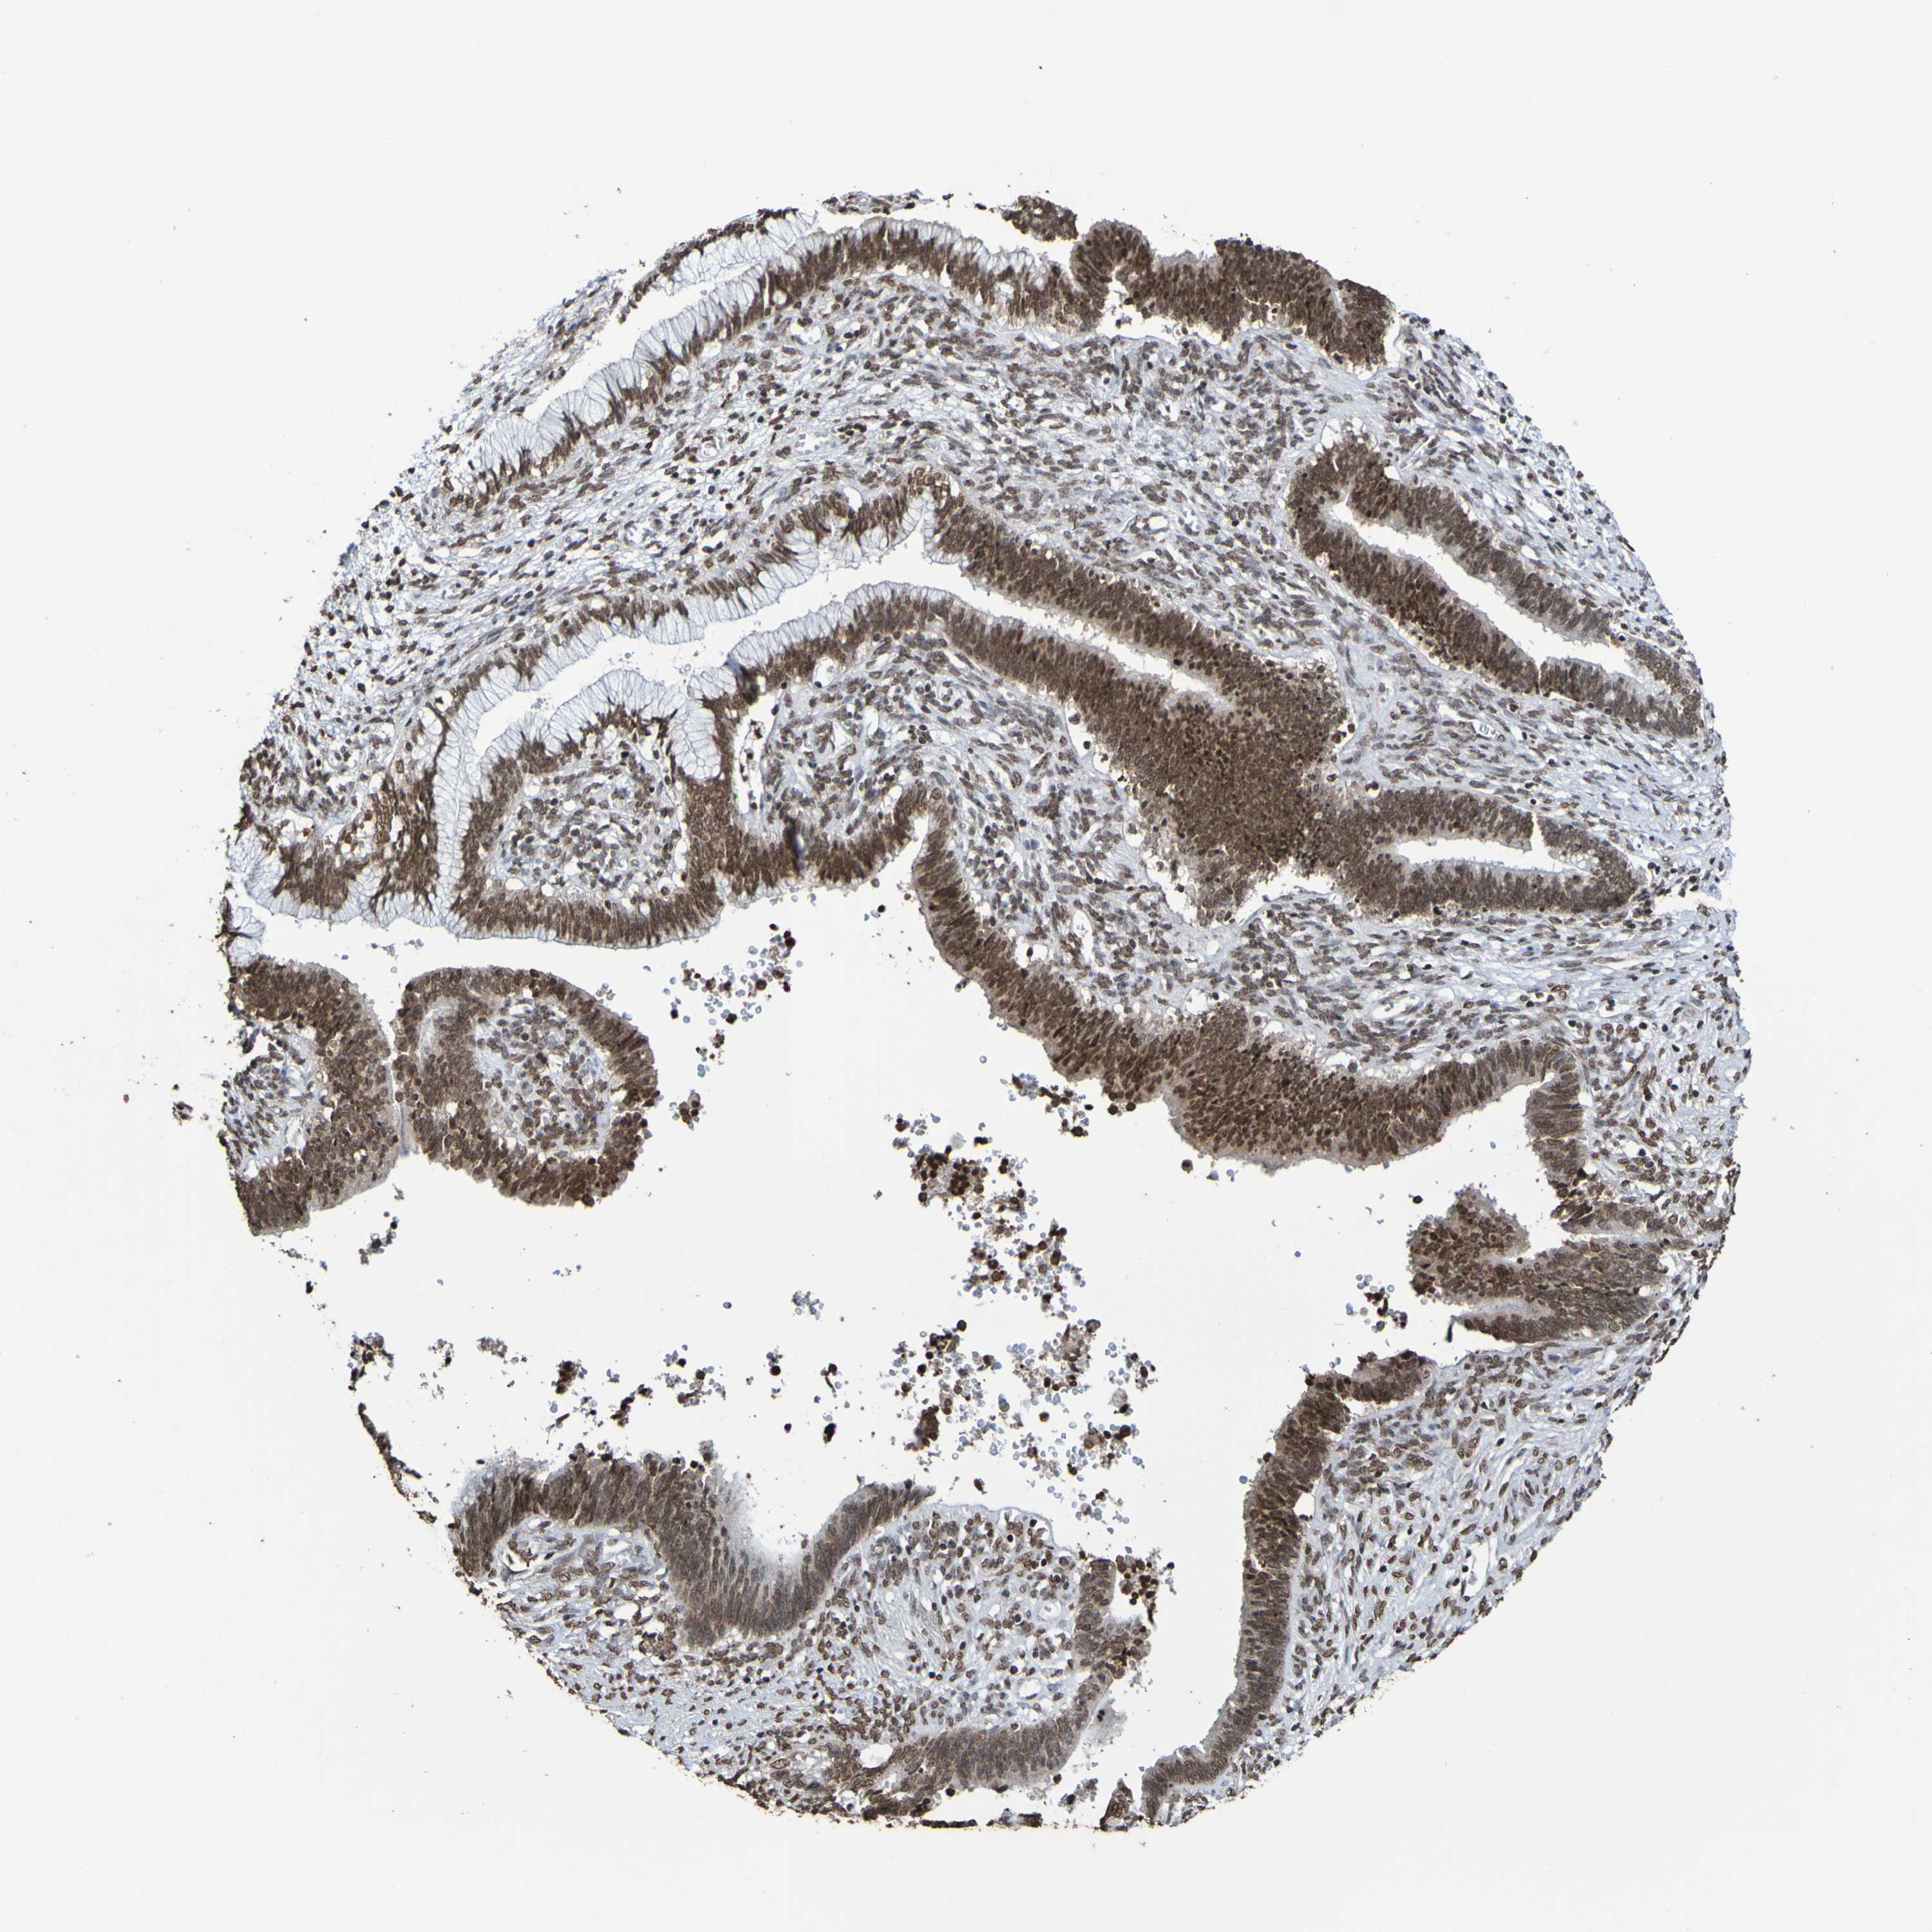

CERVICAL CANCER - Protein expressioni

A mouse-over function shows sample information and annotation data. Click on an image to view it in a full screen mode. Samples can be filtered based on level of antibody staining by selecting one or several of the following categories: high, medium, low and not detected. The assay and annotation is described here.

Note that samples used for immunohistochemistry by the Human Protein Atlas do not correspond to samples in the TCGA dataset.

Antibody stainingi

Antibody staining in the annotated cell types in the current human tissue is reported as not detected, low, medium, or high, based on conventional immunohistochemistry profiling in selected tissues. This score is based on the combination of the staining intensity and fraction of stained cells.

Each image is clickable and will lead to virtual microscopy that enables deeper exploration of all samples and also displays staining intensity scores, fraction scores and subcellular localization as well as patient and tissue information for each sample.

Antibody CAB011197

Staining

High

Medium

Low

Not detected

Intensity

Strong

Moderate

Weak

Negative

Quantity

>75%

75%-25%

<25%

None

Location

Nuclear

Cytoplasmic/membranous

Cytoplasmic/membranous,nuclear

Squamous cell carcinoma, NOS

Adenocarcinoma, NOS